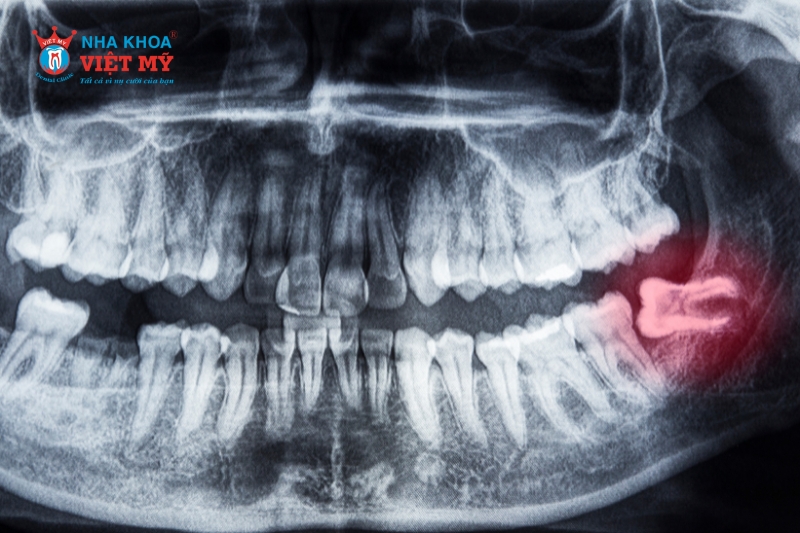

Bác sĩ sẽ tiến hành thăm khám, chụp X – Quang để xác định hình dạng, vị trí và tình trạng xương xung quanh vị trí răng cần nhổ. Từ đó, bác sĩ ước tính mức độ khó của ca tiểu phẫu và hướng nhổ răng hợp lý nhất.